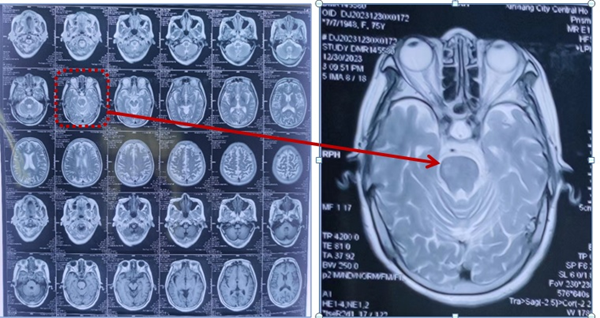

74岁的朱女士于2月余前诊断为脑干梗死,在老家医院康复科住院治疗,1月余前左肩出现疼痛伴关节活动度受限,继续在该医院治疗无效后经多方打听患者入住我科进一步治疗。入院后经专科查体及辅助检查后考虑该患者为肩关节半脱位合并肩袖损伤、左侧肱二头肌长头肌腱腱鞘炎。诊断明确后为该患者制定康复目标(强化左侧肩关节稳定性、缓解左肩关节疼痛、提高肢体实用性)。并根据该目标为患者制定了个体化康复治疗方案。经一个疗程的治疗,患者左肩关节疼痛较前减轻,夜间睡眠质量也得到改善,左上肢实用性有所提高,可以拿馒头送到嘴里,达到患者目标,出院回家。回家1周后患者家属很开心的给我发来消息,王医生,你看,我姐在跟邻居打扑克牌(要知道患者之前拒绝出门见人),这一刻,我再次理解了我工作的意义。

包括疼痛性质评价、肩关节外观、肩关节活动、肩部超声、肩关节磁共振、心理评估。